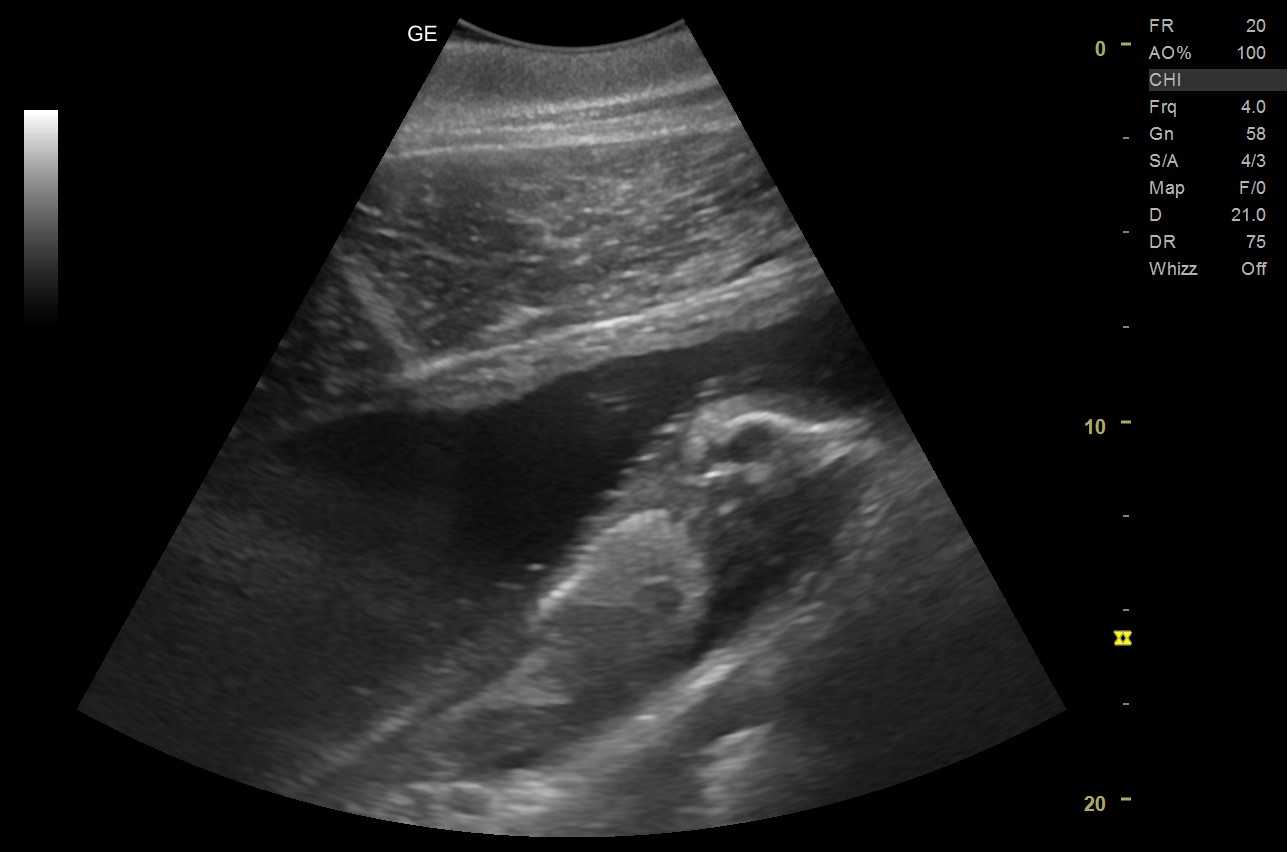

超音波検査の胎仔のようす

「テン」の妊娠については、2025年9月初旬に、体調管理のため定期的に行っている血液検査で兆候が示され、その後の超音波検査により胎仔の動きを確認しました。現在、妊娠6カ月を経過し、2026年7月上旬に出産を迎える予定です。なお、父親については、赤ちゃんの誕生後にDNA検査を行い特定する予定です。